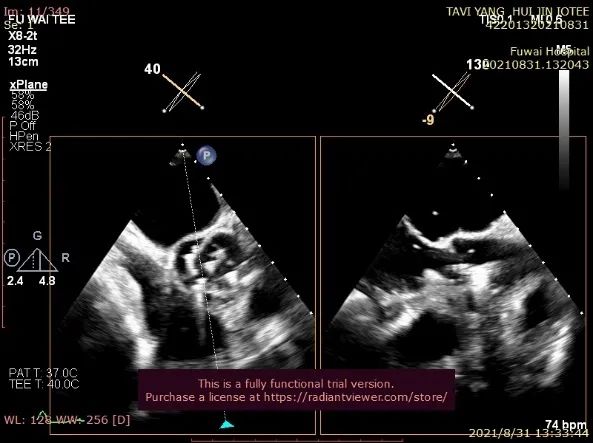

单弯管交换硬导丝后,用16F扩张鞘预扩心尖穿刺处,将 J-valve瓣膜(27号)装入输送器,将输送器推送至主动脉根部(通过零造影剂DSA确认),释放定位件,患者无需起搏,适当调整定位件角度使其进入三个主动脉窦部(图3)。

图3. TEE和放射线显示定位件入窦,人工瓣入座

通过TEE确定三个定位件准确入窦后完全释放瓣膜(图4),再次用TEE观察人工瓣膜自膨后金属支架的形态(自膨胀后最大外径)、位置(瓣环下金属支架长度及占比)、有无明显瓣周漏。撤出输送器(图5),收紧心尖处荷包线并打结,检查无出血,逐层关胸,封皮,拔出股动脉鞘并在股动脉穿刺处压迫止血。手术过程顺利,患者生命体征平稳。

图4. TEE和放射线显示人工瓣膜自膨

图5. 放射线显示锁丝松开后,输送器逐步回撤,TEE提示人工瓣(导丝处)微量中心性反流信号

术后即刻放射线显示人工瓣膜位置良好,随心跳运动,与周围组织无相对位移;TEE显示人工主动脉瓣金属支架位置良好,瓣环下支架长度约7mm,支架自膨后外径为26.8mm,接近瓣膜真实外径(图6),CDFI多角度观察,舒张期冠脉开口处血流通畅,左室流出道侧人工瓣和自体瓣环之间仅见微量反流信号(图7),收缩期人工瓣口流速良好(峰值流速:2.0m/s,峰值压差:17mmHg)(图8)。

图6. 人工瓣充分自膨后,TEE示瓣环下方金属支架长约7mm,约占瓣架总高度1/3

图7. TEE提示做冠脉开口处血流通畅,无冠窦和左冠窦交界处可见微量瓣周漏